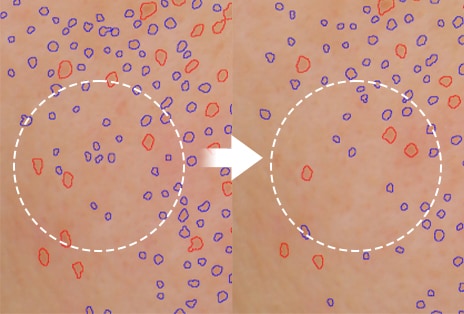

3) Excellent absorbency

-Skin Booster Boosting Mode in level 6 for 3 minutes

-Human application test results: Use of TOXNFILL Hyaluronic Boosting Ampoule / Comparison between two control groups, Skin Booster + Cosmetics vs. Hand + Cosmetics /

After absorption of the ampoule and a 30-minute wait, the degree of absorption, absorption amount, absorption depth, and absorption speed of the ampoule were measured using Raman microscopy, and the improvement rate compared to the Hand + Cosmetics control group was expressed in a %.

-February 5 - February 16, 2024 / 20 adult women (including 10 with sensitive skin) / P&K Skin Clinical Research Center

-Test results have been excerpted from the test performance report for consumer understanding.

-There may be personal differences depending on individual skin characteristics or skincare product combinations.